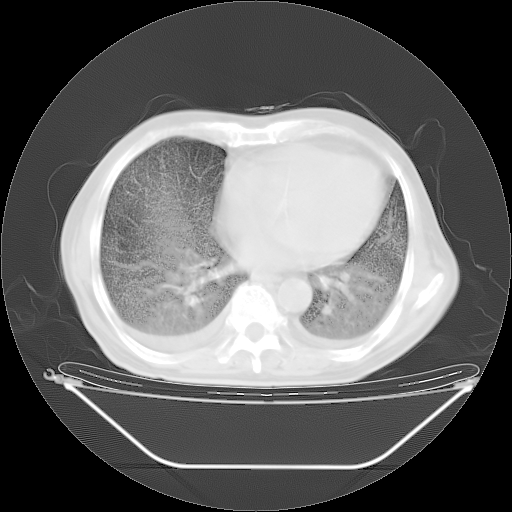

今天复查肺部CT,发现双肺广泛磨玻璃样改变。所以我把3月19日和5月9日相隔50天的肺部CT上传。请大家会诊。

2009年3月19日肺部CT片。

5月9日肺部CT(在4月27日齐鲁医院肺部CT描述部分肺组织磨玻璃样改变,12天后肺组织广泛磨玻璃样改变)